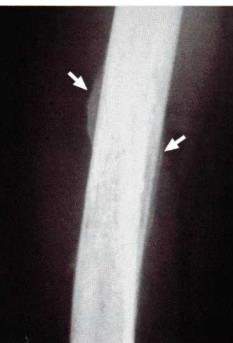

Sobre as reações periosteais, considere a radiografia de fêmur, abaixo:

Trata-se de um paciente com osteomielite do fêmur, caracterizando a reação do tipo: